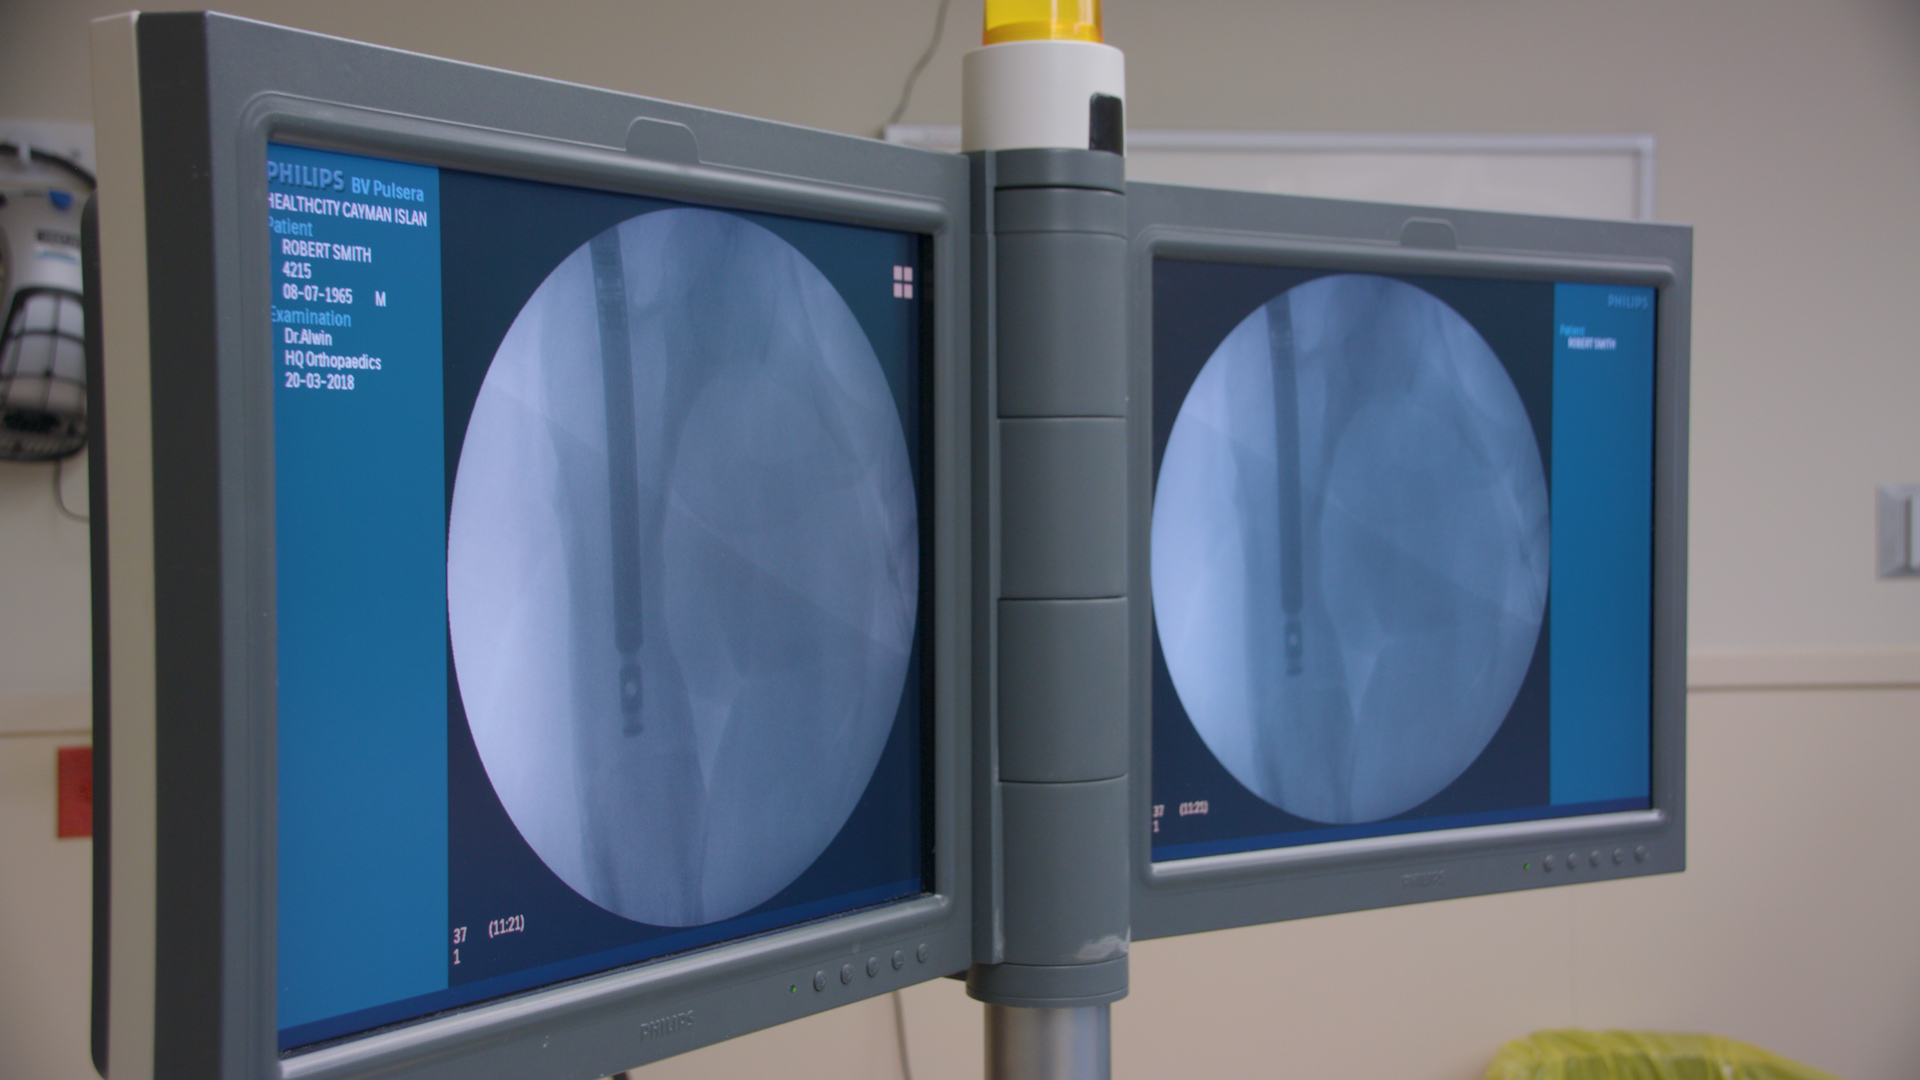

Dr. Alwin Almeida explains how the telescoping magnetic nail works to gradually extend the length of the limb.

The magnetic nail procedure, Dr. Almeida said, "allows the same lengthening without disturbing the normal anatomy of your body. It is a minimally invasive technique to insert the nail into the body with small puncture wounds. That's all there is, and even though we need to cut the bone, that is done through a minimally invasive technique."

Dr. Almeida added that "once the bone is cut, it is gradually lengthened over a period of time every day by about a millimeter and that causes more bone to form in between as it's gradually distracted ... using a magnetic nail."